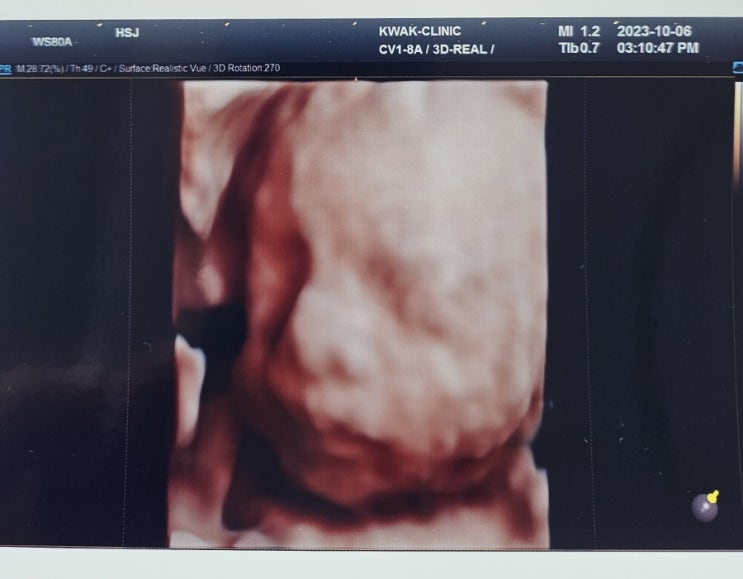

공포의 임당검사

요 며칠 나의 기분과 감정을 오르락내리락 하게했던 임당검사 포스팅 시작해본다? 지난 10월 6일 난 임...

지난번 임당검사 후, 재검하라는 연락을 받구나서 바로 오늘 재검을 받구왔다. 예상은 했으나, 생각보다 힘...